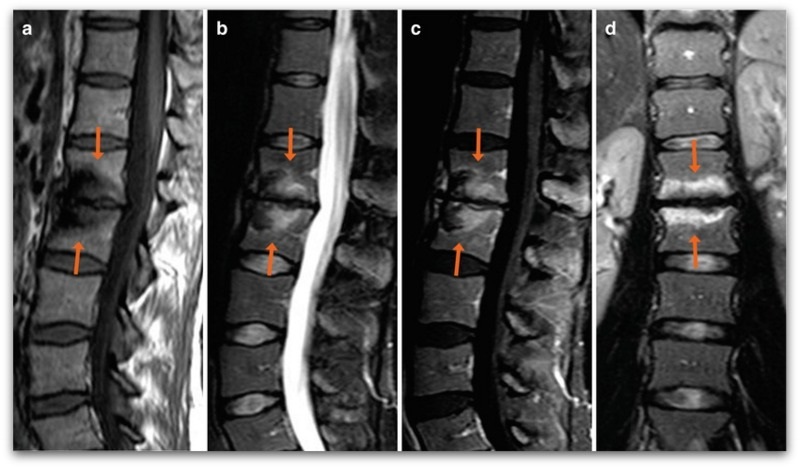

Дури 80 отсто од болката во грбот е предизвикана од остеохондроза, болест која претставува атрофија на ткивото на дискот. Големината на дисковите се намалува, апсорпцијата на потребните супстанции исто така, дисковите ја губат еластичноста и можноста правилно да ги извршуваат своите функции. Со остеохондроза, постои намалување на функциите на лигаментите и мускулите што овозможуваат дисковите да функционираат правилно, и сето ова заедно влијае на целокупната состојба на ‘рбетот.